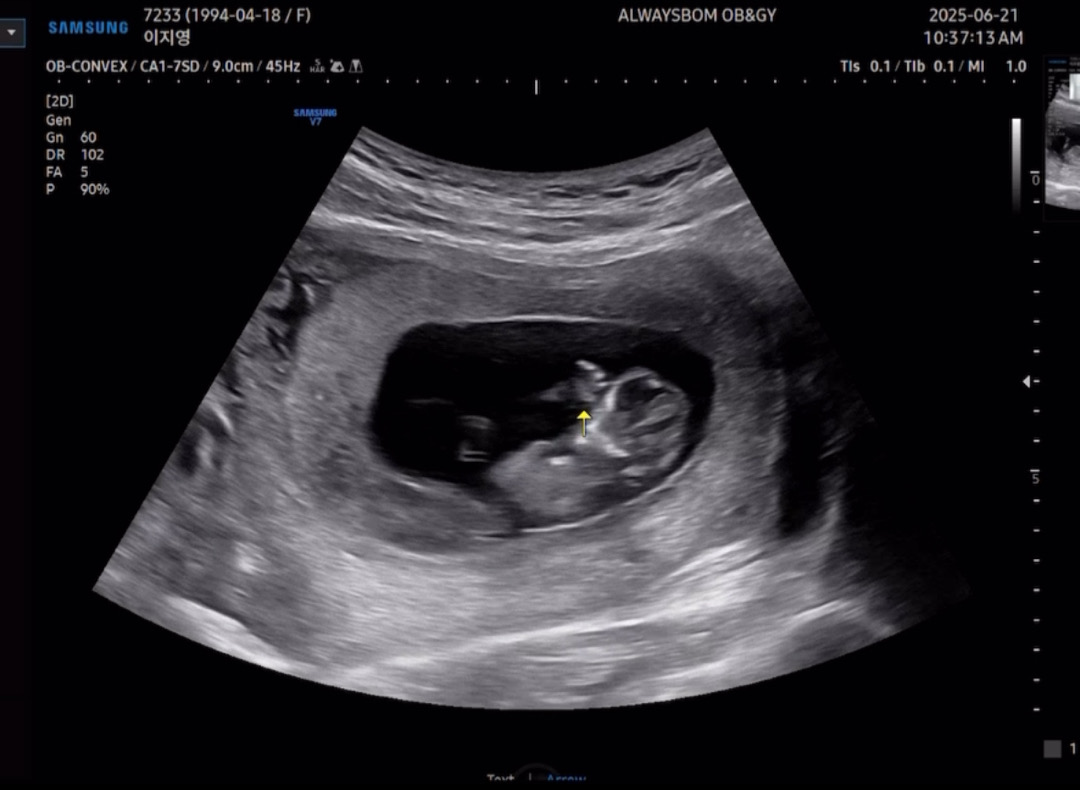

11주 3일 아가 보고왔어용

요즘 자다가 깜짝 놀래서 깨는 경우가 있어서 아가 잘 있는지 걱정되서 서브병원가서 초음파 보고 왔는데 너무 잘 놀고 있더라구요ㅎㅎ 괜한 걱정했지 뭐예요...😂 너무 잘있고 잘놀고 있어서 고맙더라구요! 작고 소중한 손가락이랑 발가락도 보구요ㅎㅎ 너무 귀여움..ㅠㅠ

헐 손빨고 노는건가요 벌써>_< 너무 귀여워요~~~

손도 빨고 이마도 짚고 있는거 같아요><ㅋㅋㅋㅋㅋㅋ